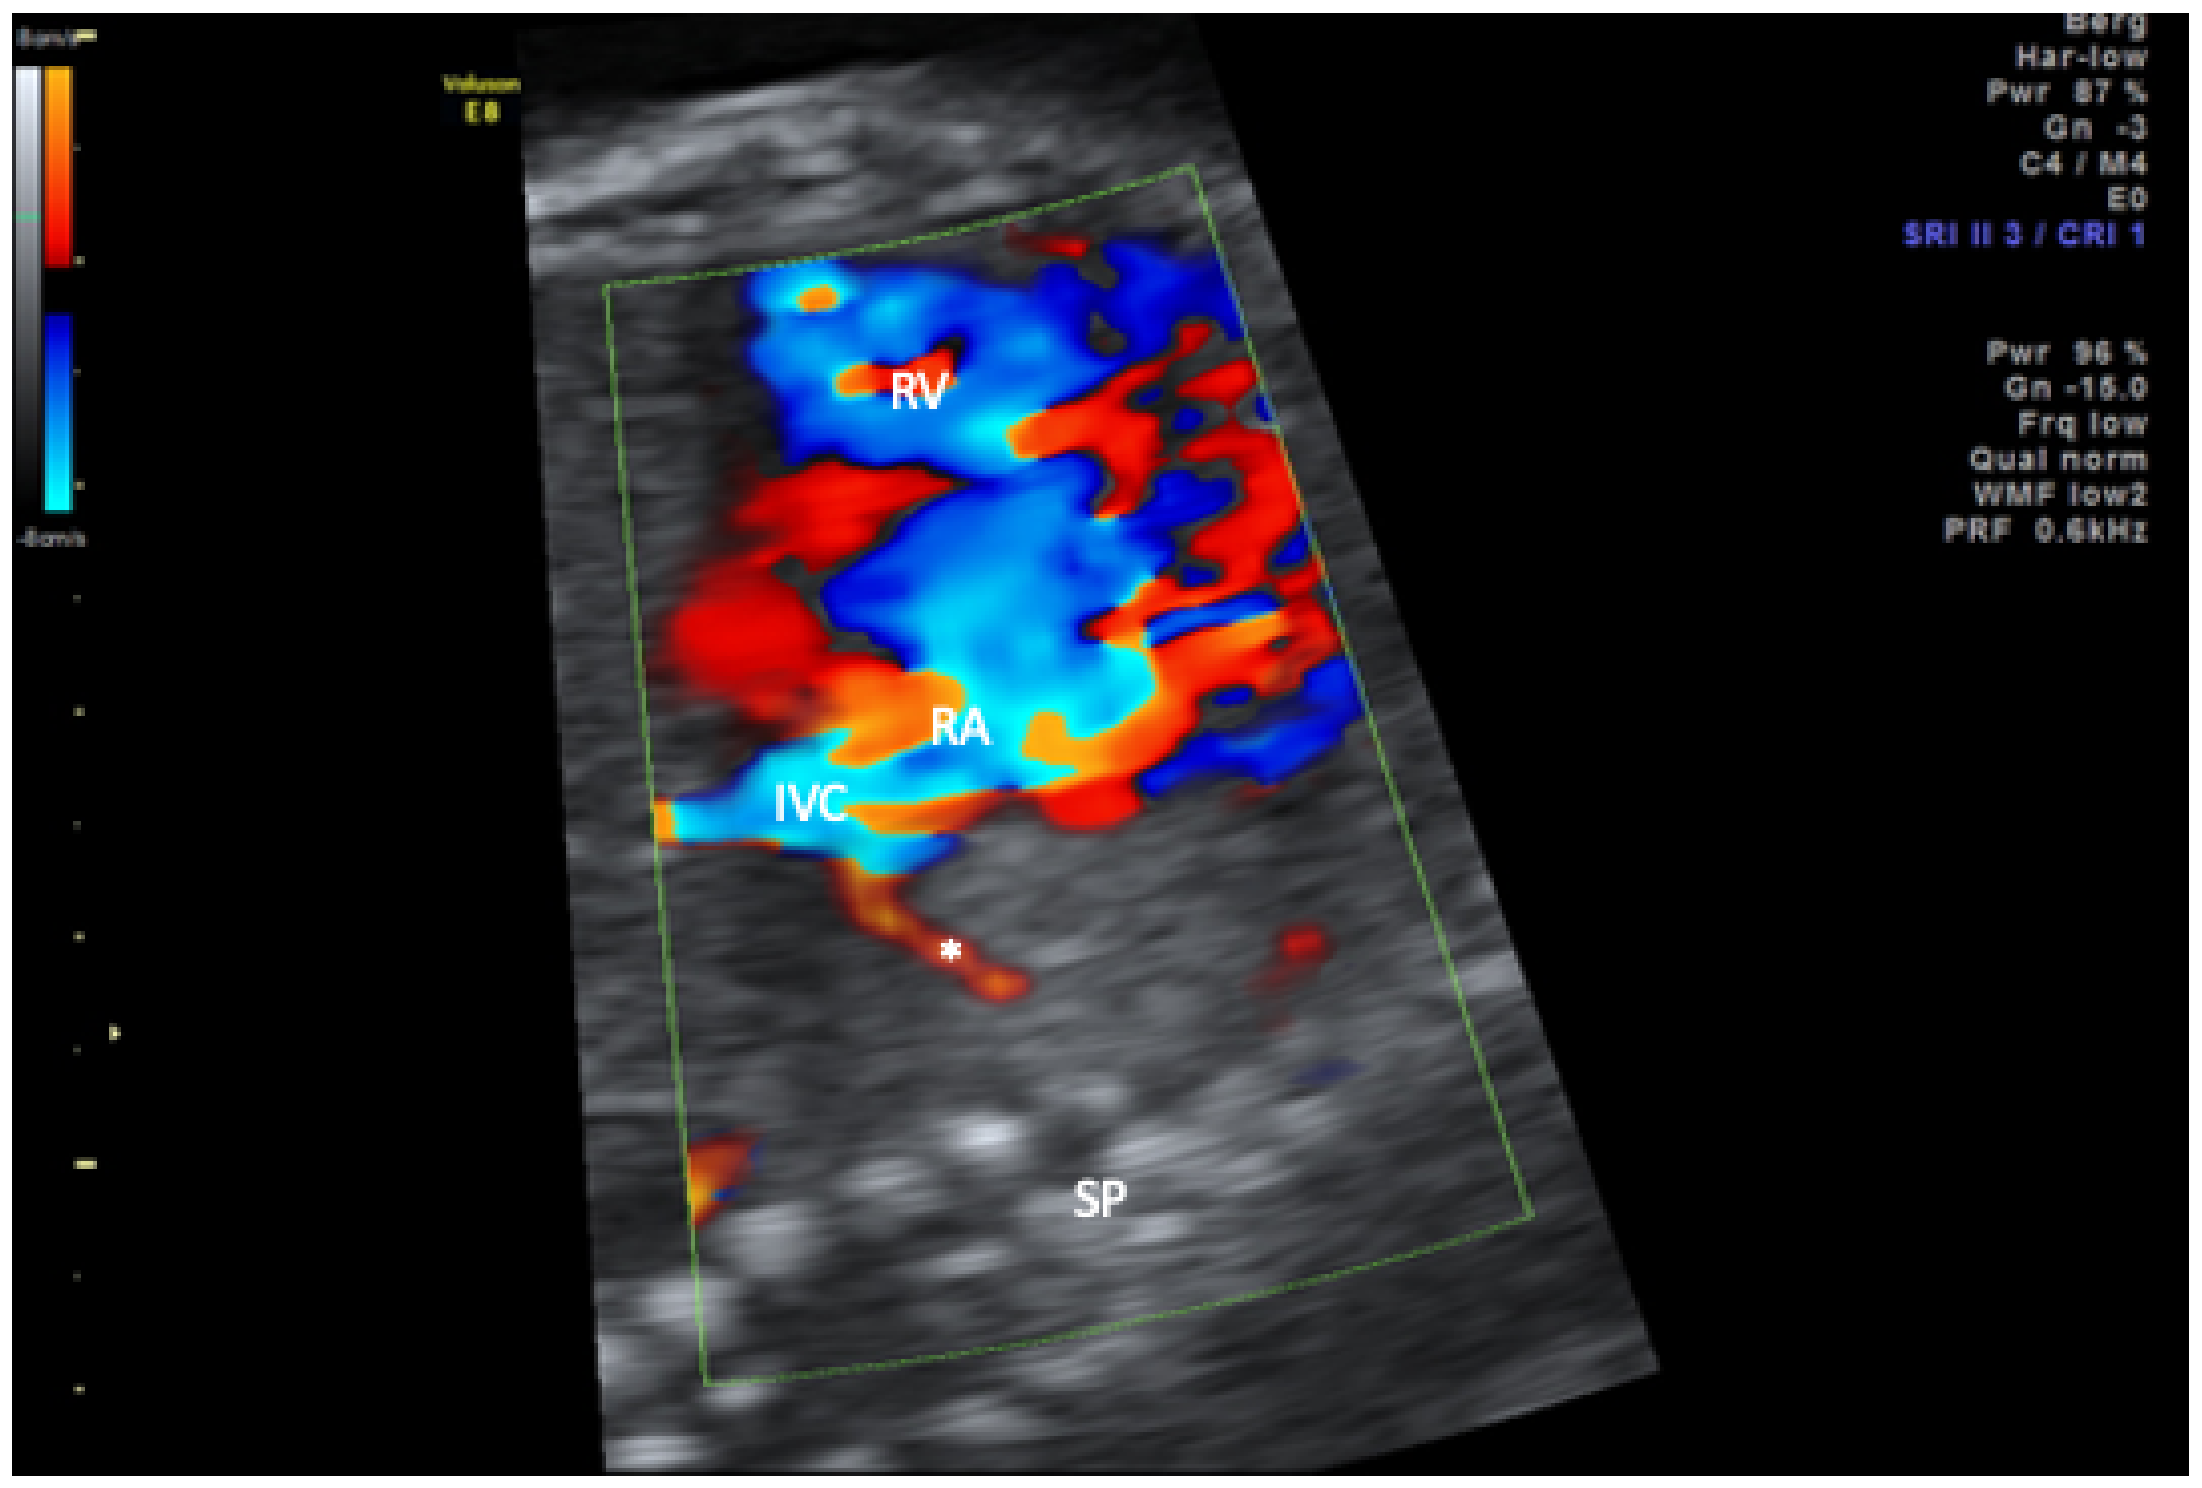

| 1 | 34 + 1 | mediastinal shift; dextroposition of the heart, right pulmonary hypoplasia, partial anomalous pulmonary drainage (scimitar vein) | 39 + 1 | Feeding vessel from coeliac trunk, secundum atrial septal defect | Coil occlusion of feeding vessel, pulmonary hemorrhage with respiratory deterioration, intracranial hemorrhage, diabetes insipidus centralis, exitus at 1 month |

| 2 | 38 + 0 | mediastinal shift; dextroposition of the heart, right pulmonary hypoplasia, partial, anomalous pulmonary drainage (scimitar vein), right sided diaphragmatic hernia; coarctation; duplication 10q22.1–10q23.2 | 39 + 2 | Feeding vessel from abdominal aorta, pulmonary hypertension | Coil occlusion of feeding vessel, intractable pulmonary hypertension, exitus at 6 months |

| 3 | 20 + 2 | mediastinal shift; dextroposition of the heart, right pulmonary hypoplasia, partial anomalous pulmonary drainage (scimitar vein) | 35 + 5 | Feeding vessel from abdominal aorta, hypoplastic aortic arch; secundum atrial septal defect; anomalous supracardiac pulmonary drainage of left pulmonary veins in brachiocephalic vein | Plug occlusion of feeding vessel, reinsertion of left pulmonary veins, patch reconstruction of aortic arch, postoperative hydrocephalus; hypoplastic corpus callosum; ventilation malfunction hypoxic crisis with bradyasystole, exitus at 6 months, |

| 4 | 31 + 1 | mediastinal shift; dextroposition of the heart, right pulmonary hypoplasia, anal atresia, diaphragmatic hernia, hemivertebrae, single umbilical artery, renal dysplasia | 33 + 6 | partial anomalous pulmonary drainage (scimitar vein), Feeding vessels from thoracic aorta, hypoplastic aortic arch, secundum atrial septal defect, VACTERL association | Plug occlusion of feeding vessel and 2 MAPCAs in neonatal period, multiple bronchial stent placements, 4 years old |

| 5 | 22 + 2 | mediastinal shift; dextroposition of the heart, right pulmonary hypoplasia, partial anomalous pulmonary drainage (scimitar vein) | 31 + 0 | Feeding vessel from coeliac trunk, secundum atrial septal defect, mild coarctation | Plug occlusion of feeding vessels in neonatal period, thriving with mild pulmonary hypertension, 7 years old |

| 6 | 17 + 2 | mediastinal shift; dextroposition of the heart, right pulmonary hypoplasia, partial anomalous pulmonary drainage (scimitar vein), single umbilical artery, left persistent superior caval vein | 40 + 0 | 2 Feeding vessels from thoracic aorta, anomalous drainage of right sided pulmonary veins in left atrium, secundum atrial septal defect | Plug occlusion of feeding vessels in neonatal period and at age of one year. Correction of right pulmonary veinous drainage with intra-atrial tunnel and ligation of persisting ductus arteriosus at age of 2 years, infantile cerebral palsy; tracheostoma; Percutaneous endoscopic gastrostomy(PEG) placement, 10 years old |